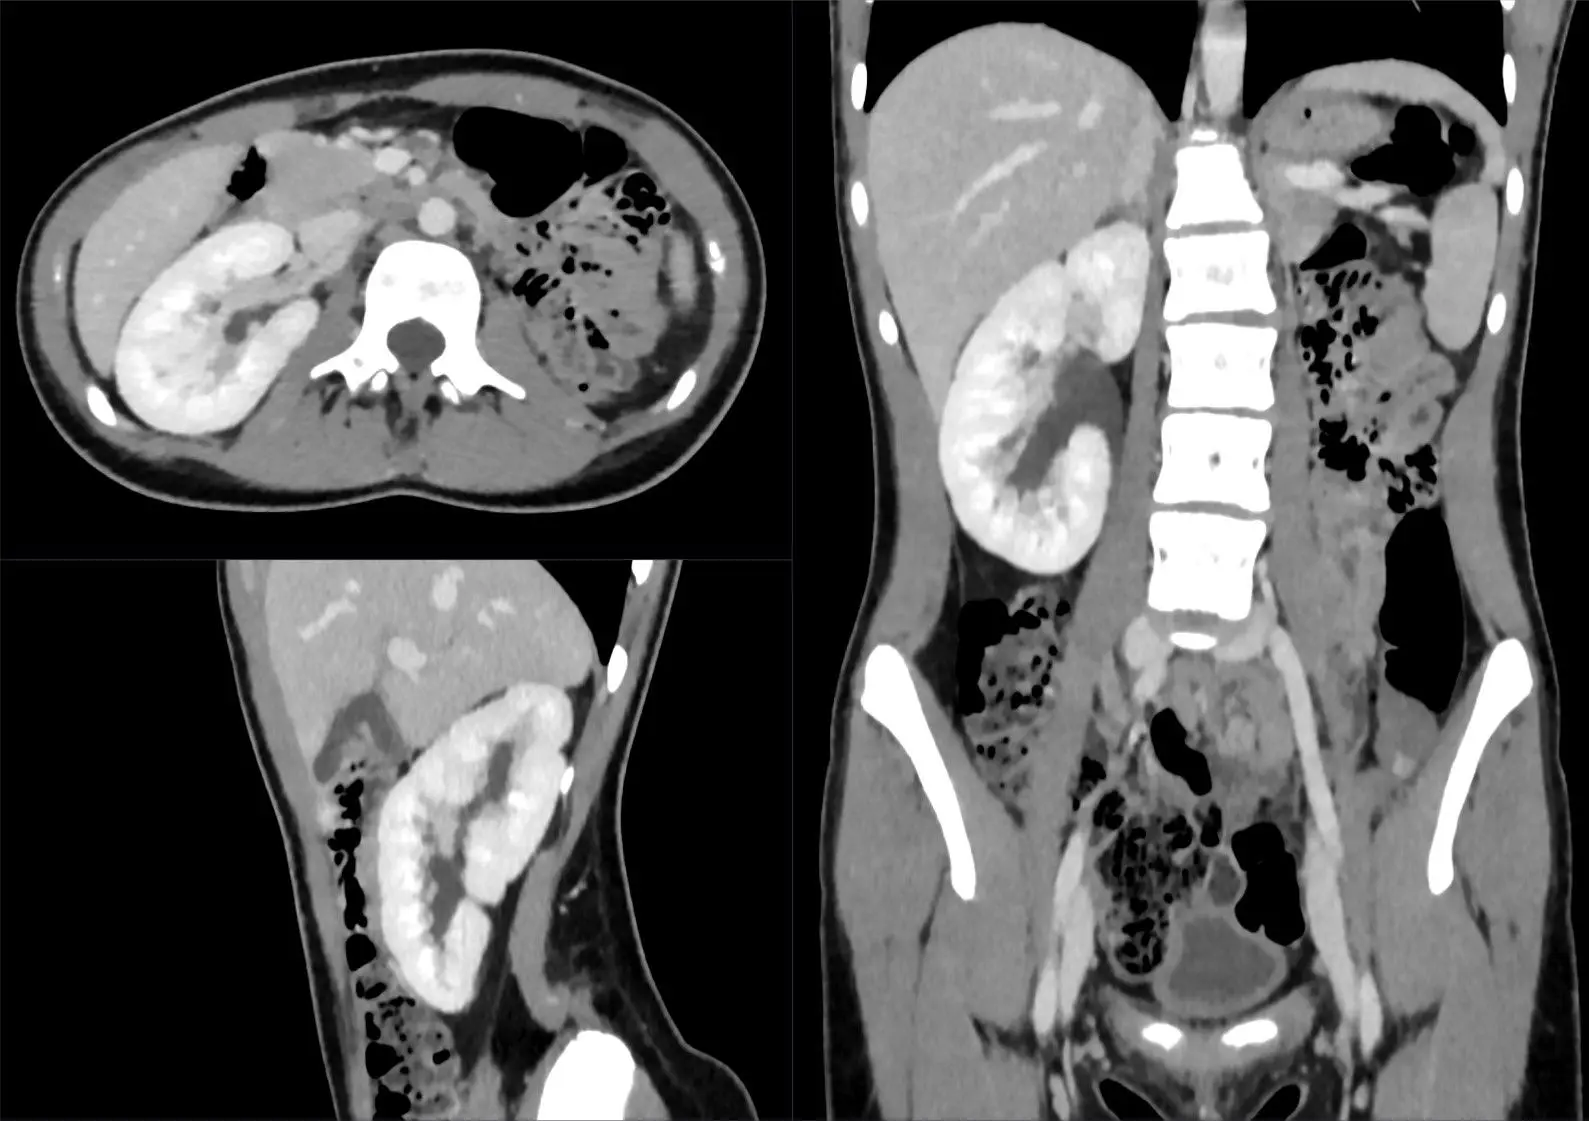

Die Diagnose einer einseitigen Nierenentwicklung kann bereits während der Schwangerschaft oder kurz nach der Geburt gestellt werden. Eine Ultraschalluntersuchung des Bauches kann die Größe und Funktion der Nieren beurteilen.